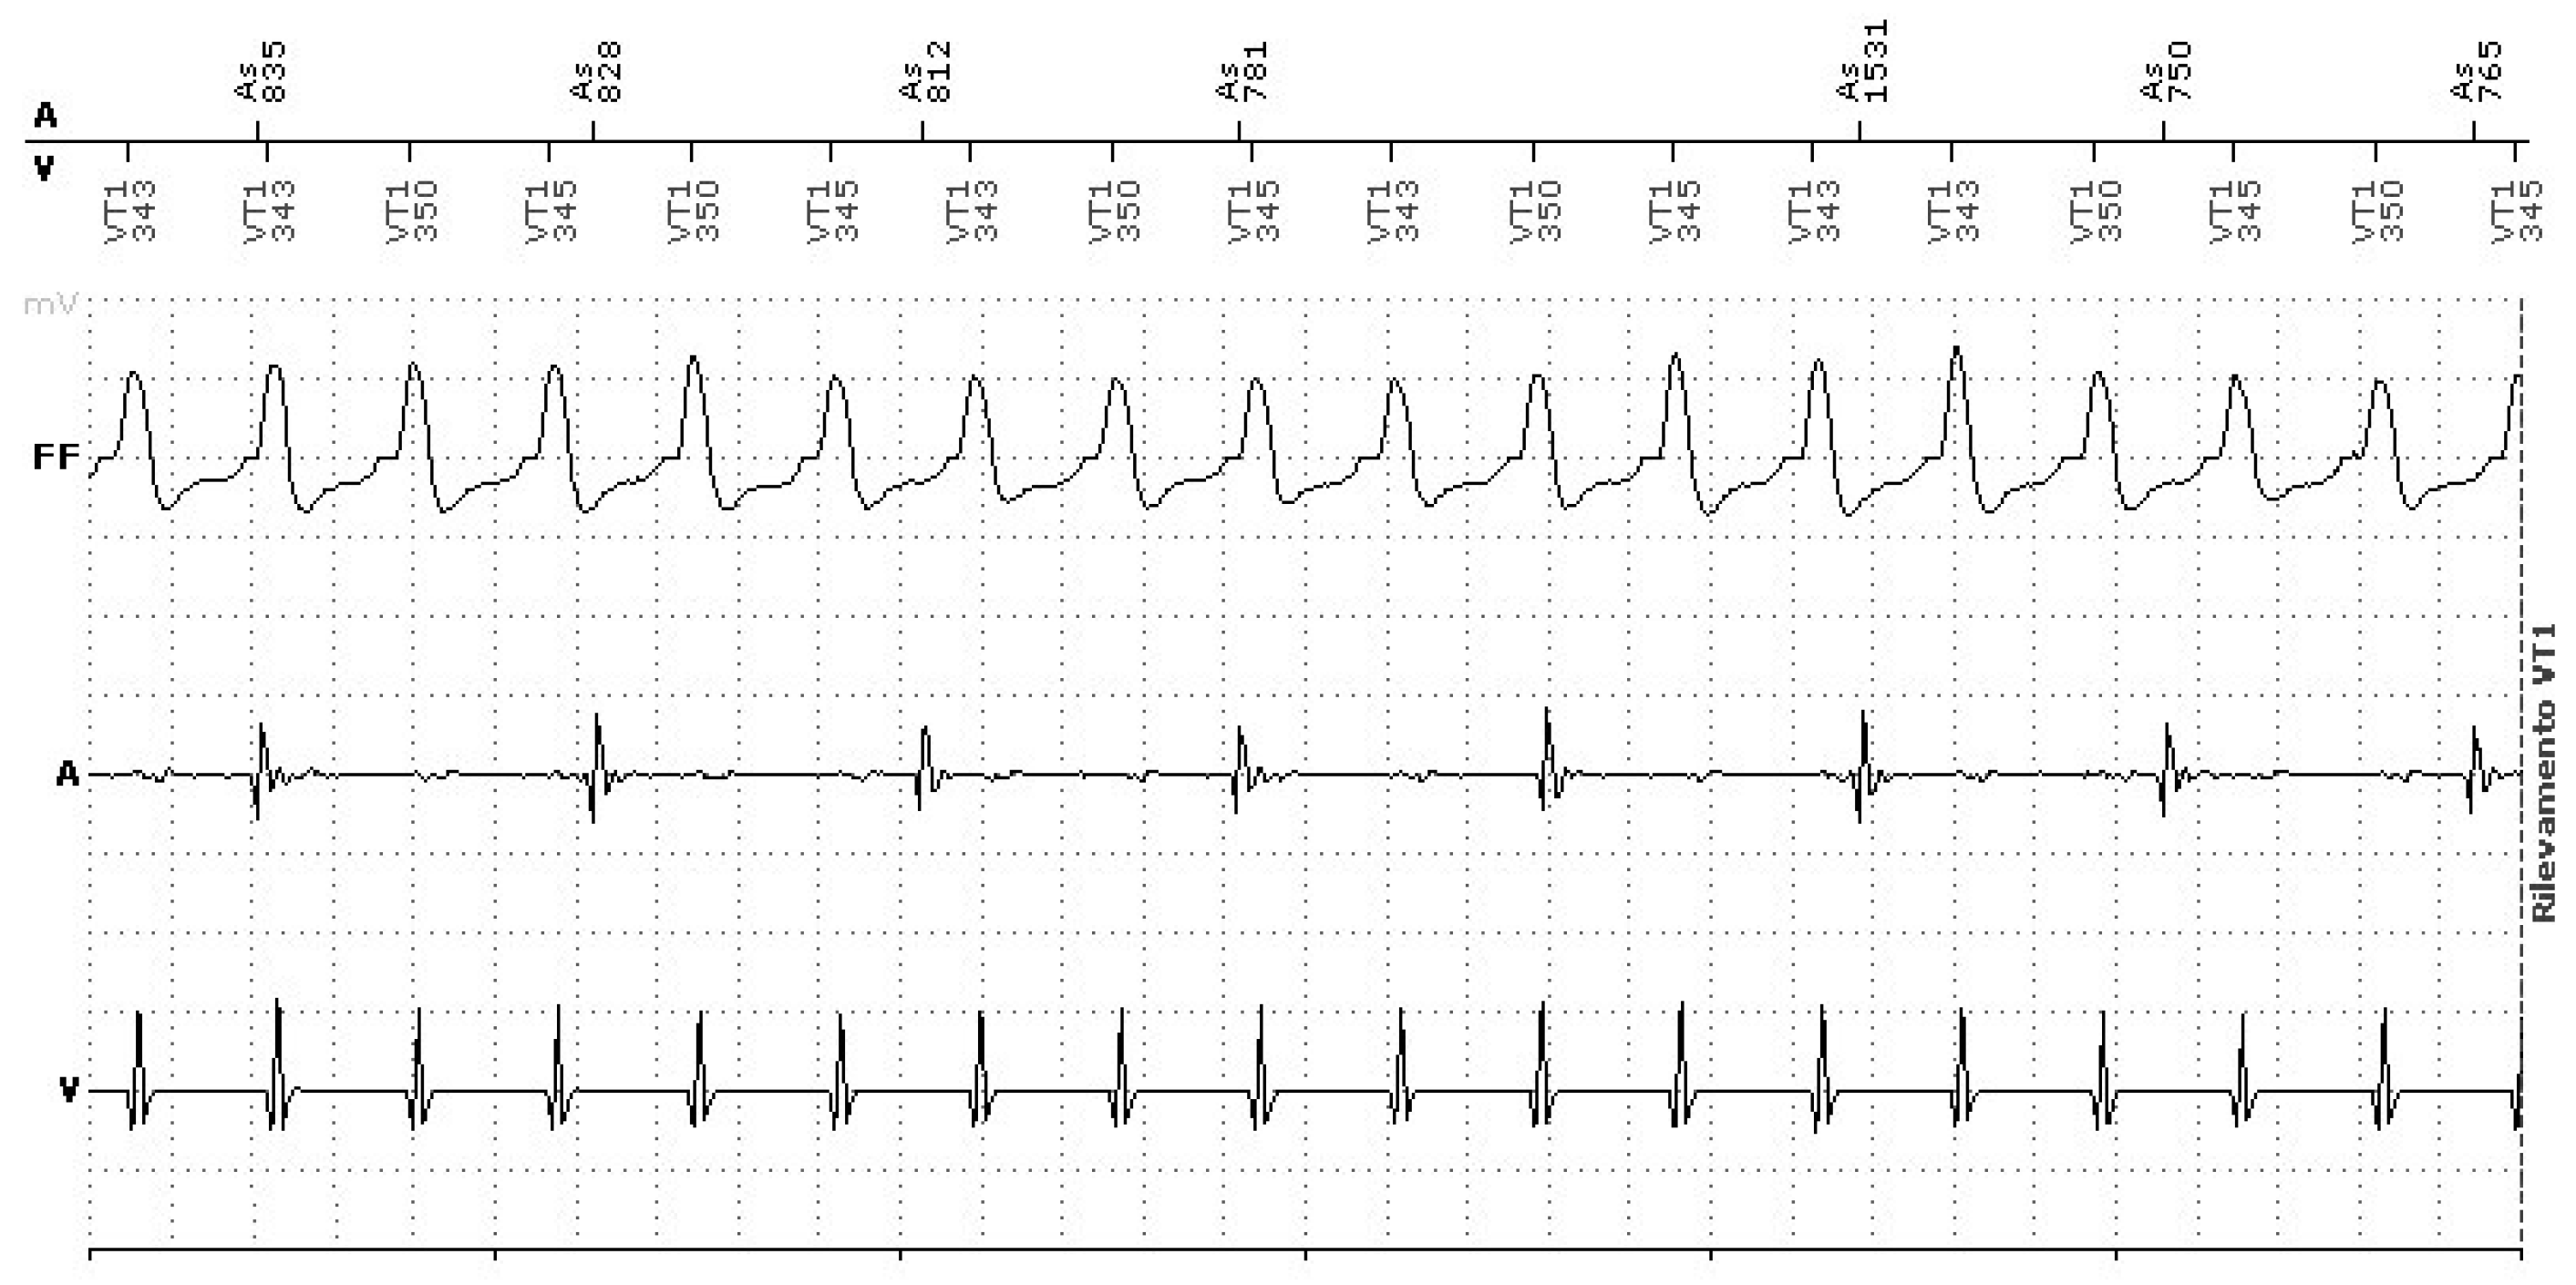

3.1.4. Short-Long-Short Sequences Promoting Ventricular Tachyarrhythmias